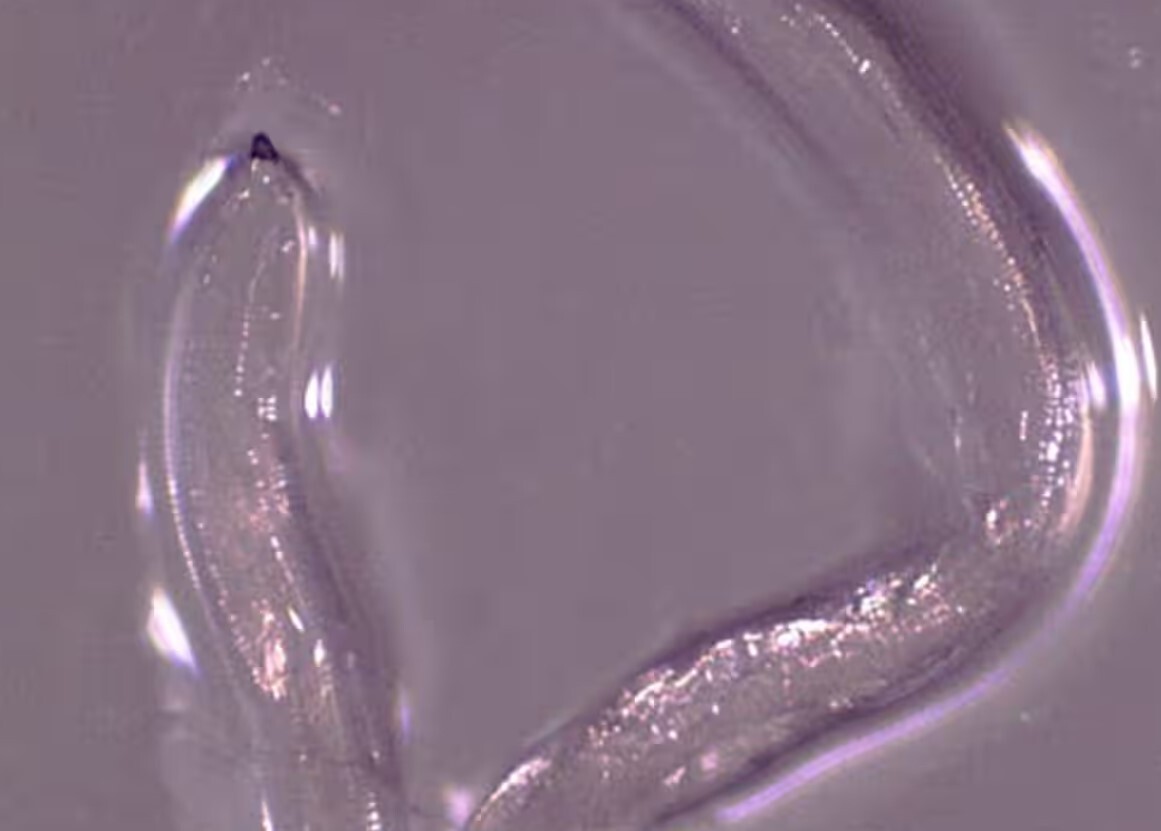

زنی در اورگان کشف شد که دارای نوعی کرم چشم بود که پیش تر صرفا در یک گاو در سال 2018 میلادی مشاهده شده بود. لاروهای کرم توسط مگس هایی که از اشک گاو تغذیه می کنند برداشته و پخش می شوند. این زن 26 ساله پس از اسب سواری در گلد بیچ شهری در شهرستان کاری ایالت اورگان منطقه ای که در آن گاوها پرورش پیدا می کنند یک هفته سوزش چشم را تجربه کرده بود. علت آن سوزش زمانی کشف شد که او یک کرم کوچک را از چشم چپ اش بیرون کشید. او به دنبال کمک پزشکی و درمانی بود و 14 کرم متعاقبا ا چشم اش خارج شدند که بیشتر آن ها توسط شخص بیمار بیرون کشیده شدند. این کرم‌های کوچک هر کدام کم تر از یک سانتی ‌متر طول دارند و از گونه ‌ای به نام Thelazia gulosa هستند. دکتر "ریچارد بردبری" نویسنده اصلی مطالعه ای که این مورد را گزارش کرد و با بخش بیماری های انگلی و مالاریا در مرکز کنترل و پیشگیری از بیماری های ایالات متحده کار می کند در آن زمان گفت که این عفونتی نادر بوده است.

او افزود:"عفونت ناشی از کرم های تلازیا عمدتا در حیوانات رخ می دهد و انسان ها صرفا میزبانان اتفاقی آن هستند. این موضوعی فوق العاده جالب است. با این وجود، این موضوعی نیست که باعث ایجاد نگرانی عمده و عمومی شود".